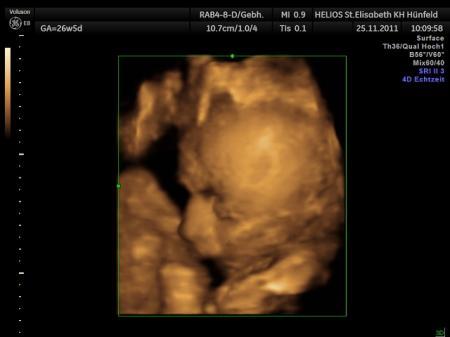

Hey ich kugelinnen :-) alles super verlaufen heute. Meine Maus hat ein gewicht von 1650 g und ne Größe von 40 cm also bekomme ich ne ne KLEINE süße Maus :-) der Termin für den KS steht auch, verrate ich aber jetzt noch nicht. und es wird so wie Operierender Arzt und Hebamme sagten mit sehr großer wahrscheinlichkeit ein KS unter voll Narkose. zum Narkose arzt soll ich erst 3 Wochen vor der geburt, eher will der mich nicht sehen LG Nienchen mit Baby Leandra im Bauch

muss mich mal bei den Daten verbessern... hatte die augen nicht richtig auf gehabt *lach* das ca, gewicht beträgt nicht 1650 g sondern 1701g. na ja kann ja mal passieren.